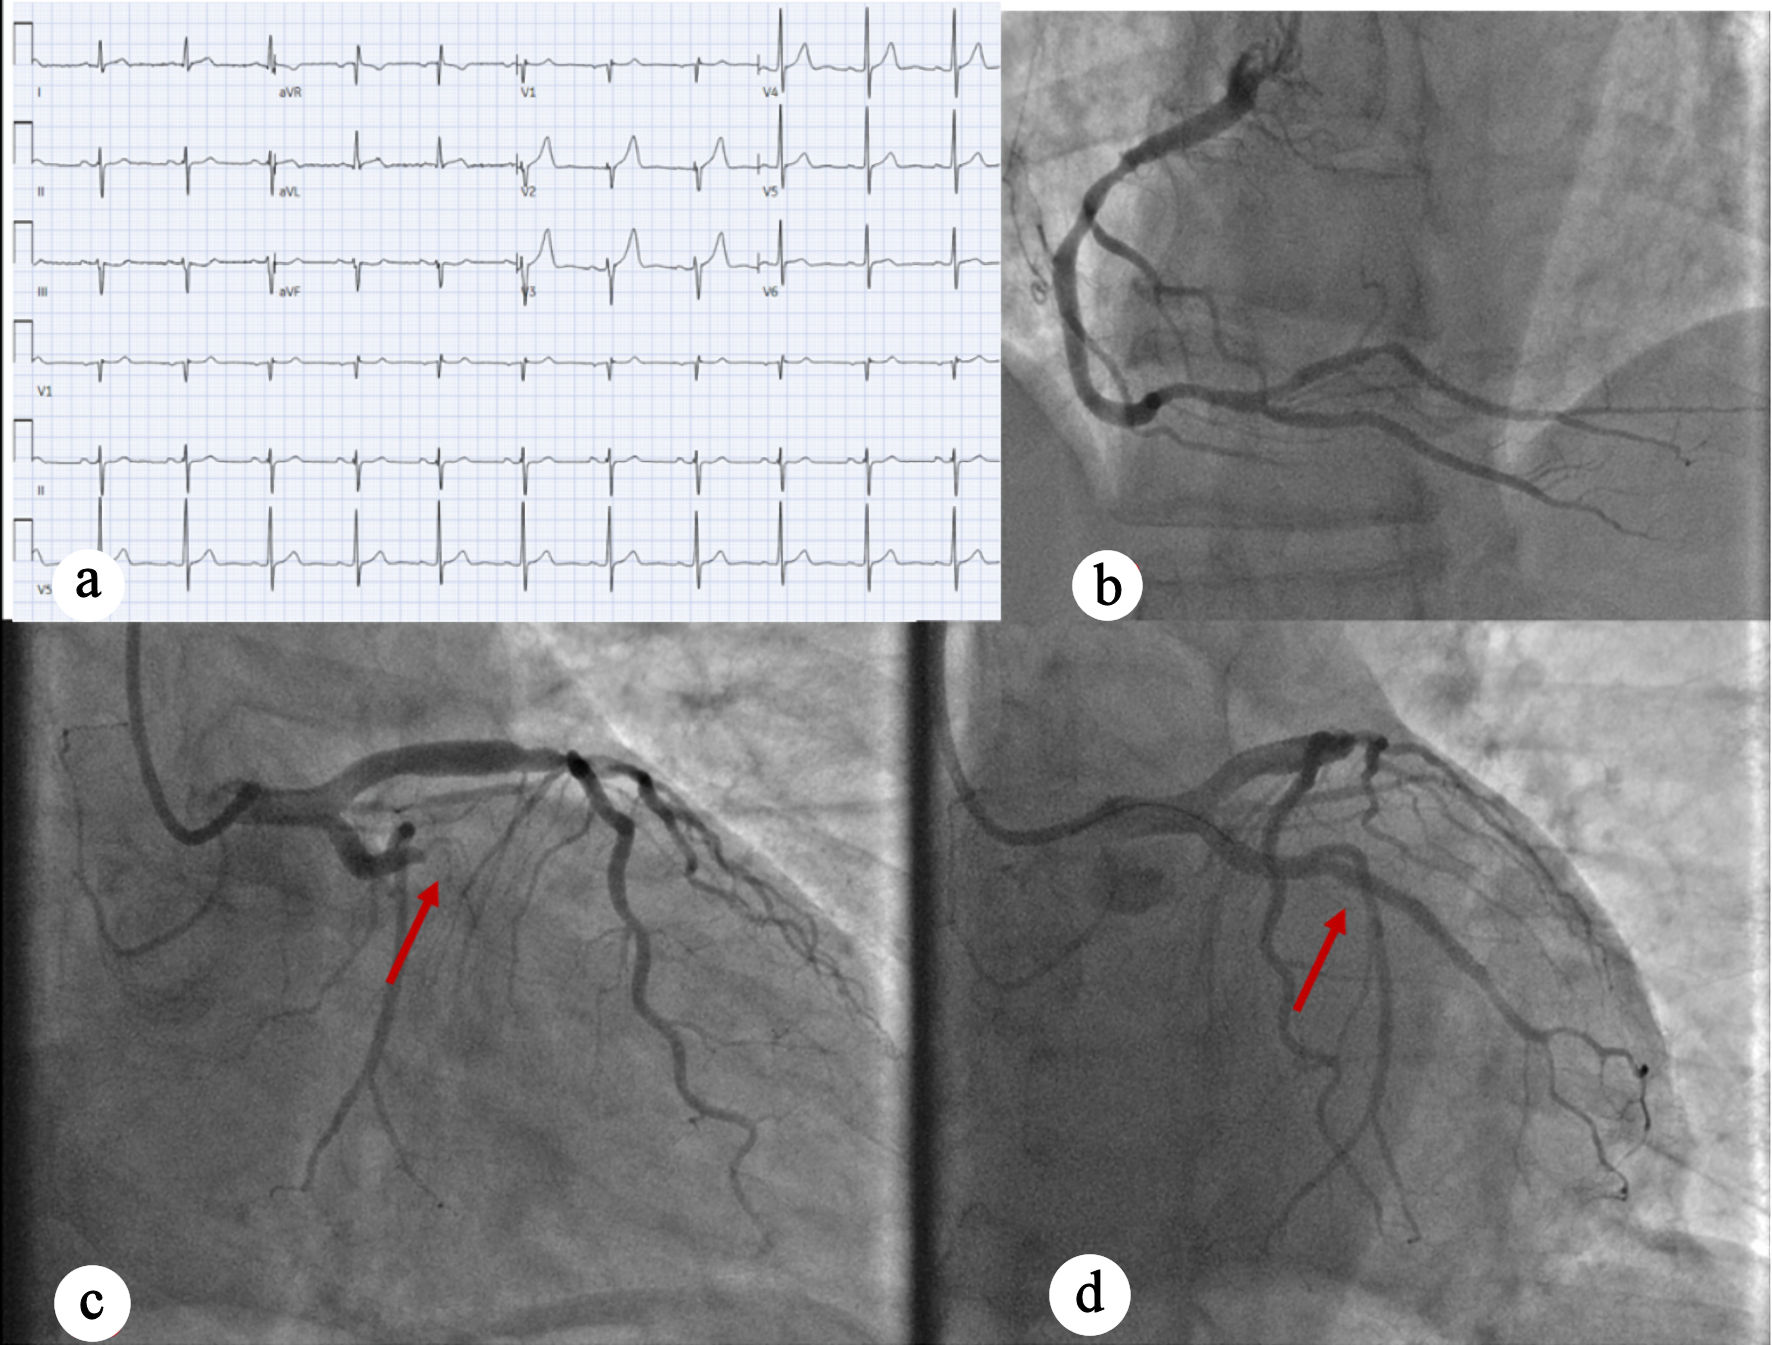

A 45-year-old man with no significant past medical history presented with chest discomfort, low-grade fever, body aches, and fatigue for 3 days. The chest pain was left-sided and radiated to his back. He denied palpitations, orthopnea, paroxysmal nocturnal dyspnea, abdominal pain, nausea, or vomiting. The patient’s family history is significant for myocardial infarction in his father at age 53. In the ED, he was hypotensive (96/62 mm Hg), but otherwise hemodynamically stable. Labs were notable for elevated troponins at 4.45 ng/mL. EKG again was nondiagnostic for ischemia (Fig. 3a). Cardiology was consulted for NSTEMI, and the patient was loaded with aspirin, ticagrelor and intravenous heparin. He was admitted to the CCU for further management. TTE showed normal LV size and wall thickness with preserved systolic function (EF 55-60%), no regional wall motion abnormalities, grade I diastolic dysfunction, and trace mitral regurgitation. As the patient continued to experience chest pain, the IC team was activated. LHC showed single-vessel CAD with 90% stenosis of the proximal Ramus intermedius, which was treated with DES (Fig. 3b–d). During the procedure, transient occlusion of the LAD and LCX occurred, with suspected secondary air embolism versus thrombus that resolved with heparinized saline. Intraoperatively, the patient developed ventricular tachycardia and new ST elevations, which required a rapid response evaluation. A second rapid response was called for acute hypoxic respiratory failure with concern for flash pulmonary edema in the setting of elevated left-sided pressures requiring intubation and mechanical ventilation. The patient was noted to be hypotensive and required initiation of norepinephrine and dopamine for cardiogenic shock. An intra-aortic balloon pump (IABP) was placed through the right femoral artery with 1:1 augmentation. The patient was transferred to the CCU with gradual improvement. He was extubated, vasopressors and oxygen requirements were down-titrated, and the IABP was removed. TTE performed 2 days post-LHC revealed normal LV size and wall thickness with preserved systolic function (EF 70-71%), no regional wall motion abnormalities, grade I diastolic dysfunction, and trace mitral and tricuspid regurgitation. Troponin levels initially trended upward during hospitalization and were followed until a downward trend was observed. The patient was hemodynamically stable and was discharged after 11 days with follow-up.

Figure 3. (a) EKG showing normal sinus rhythm with no ischemic changes. (b) Right anterior oblique caudal view showing normal RCA. (c) Coronary angiography indicating 90% proximal ramus intermedius stenosis (red arrow). (d) Left anterior oblique caudal view post-PCI perfusion of ramus intermedius (red arrow). EKG: electrocardiogram; RCA: right coronary artery; LAD: left anterior descending artery; OM: obtuse marginal artery; PCI: percutaneous coronary intervention.